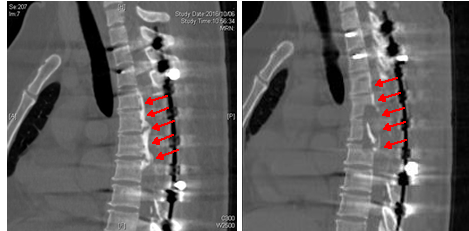

図 胸椎後縦靭帯骨化症の手術

(左)術前CTでは、胸椎高位に著明な後縦靭帯の骨化がみられます。

(右)術後CTでは、後縦靭帯の骨化が完全に切除されていることが分かります。